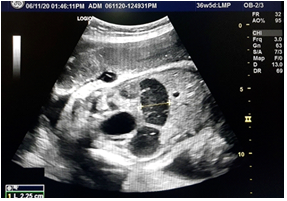

A 32 year old pregnant female came for her routine antenatal scan at 36 weeks of gestation whose anomaly scan at 18 weeks of gestation was apparently normal. Antenatal scan at 36 weeks of gestation showed a large segment of dilated bowel loop measuring 10cm in length and 2.25cm in width with normal nondilated stomach and normal amniotic fluid for gestation (Figure 1).

Figure 1: Antenatal ultrasound showing dilated bowel loop